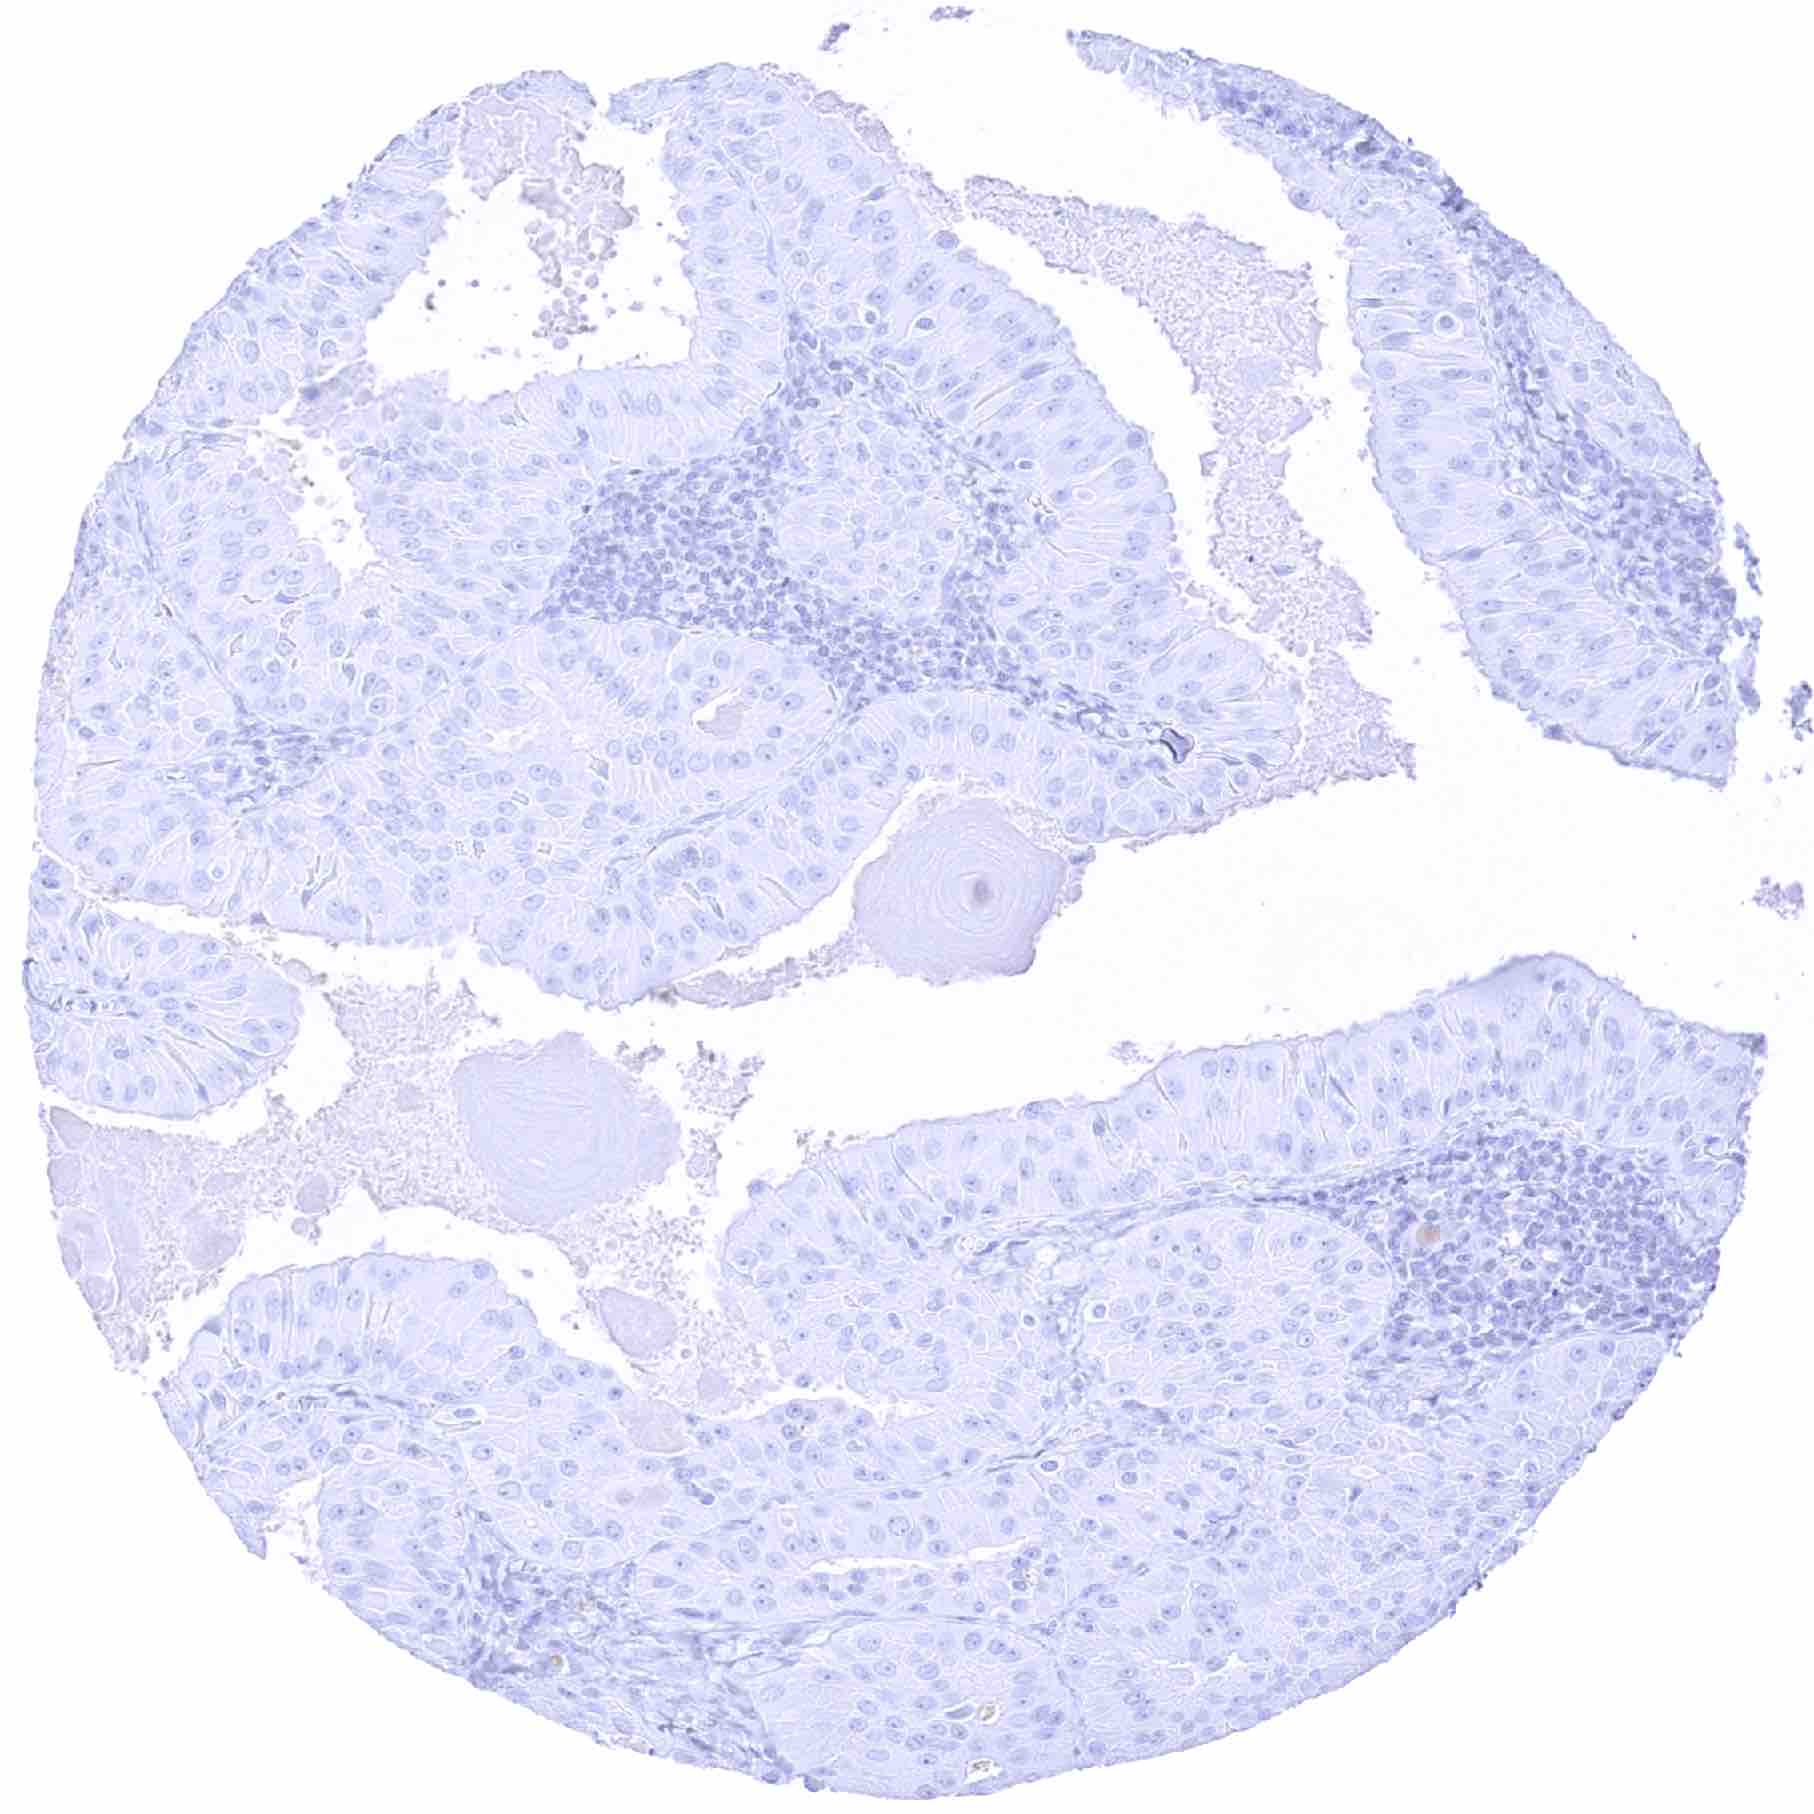

Testis – StAR negative seminoma containing groups of interspersed StAR positive Leydig cells